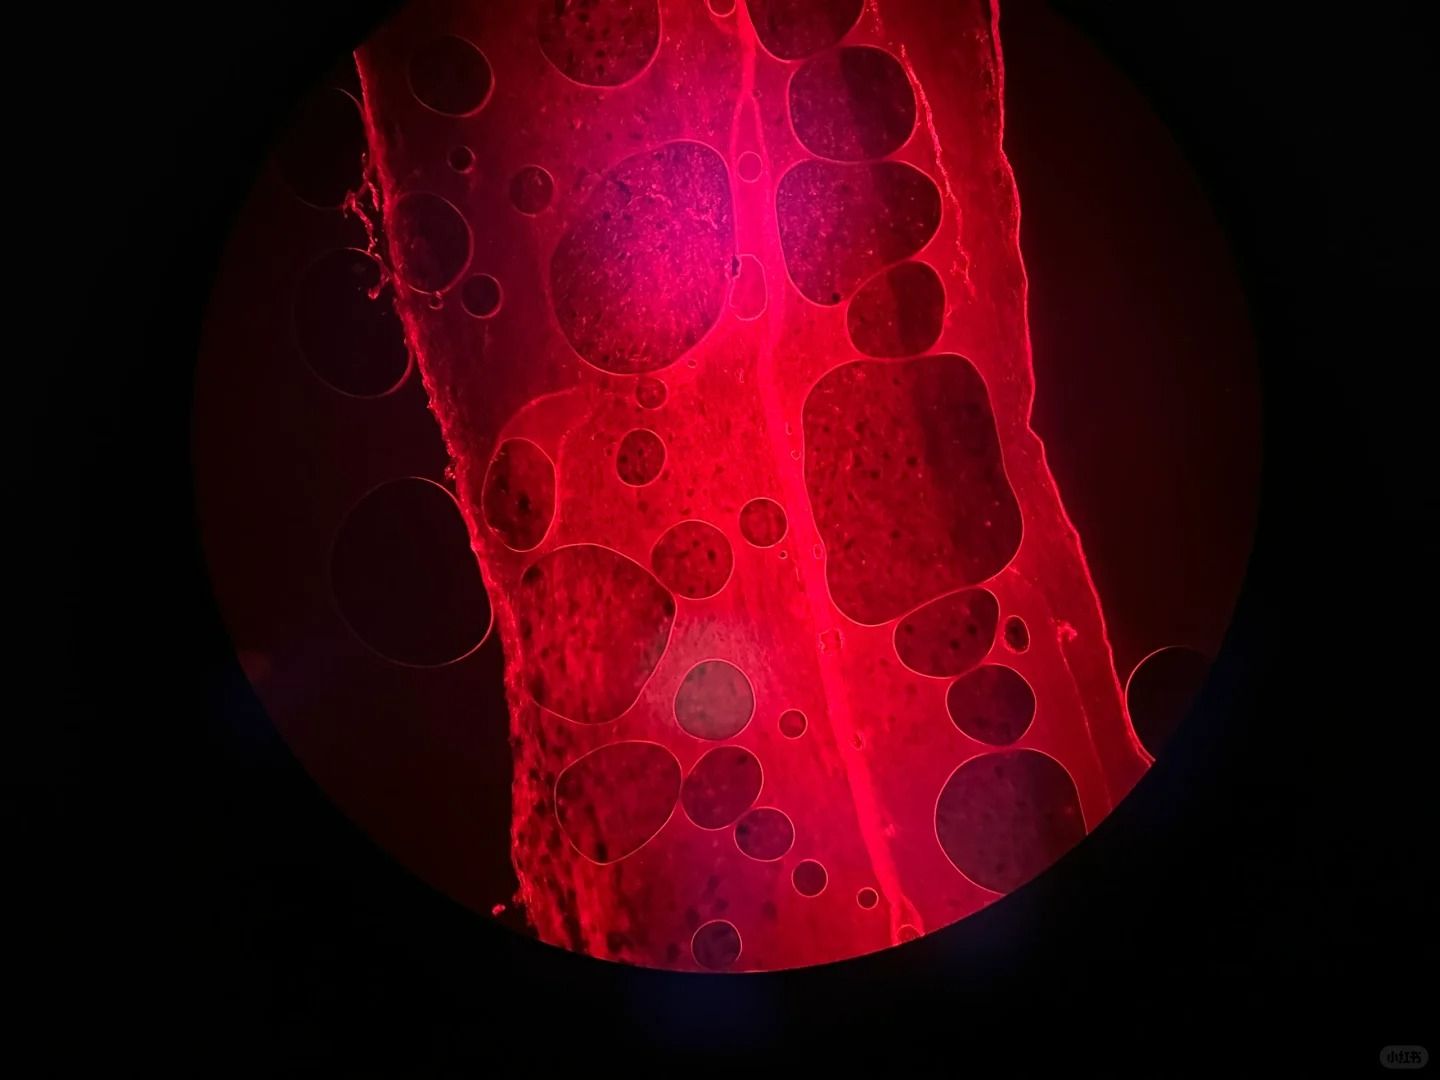

六、切片表面有氣泡

切片表面出現(xiàn)氣泡,可能是組織冷凍時內(nèi)部含有過多水分或空氣造成的。

為了消除氣泡,我們可以嘗試以下方法:

①在組織冷凍前,用吸水紙輕輕吸去組織表面的多余水分。

②在切片過程中,輕輕按壓切片,幫助排除氣泡。